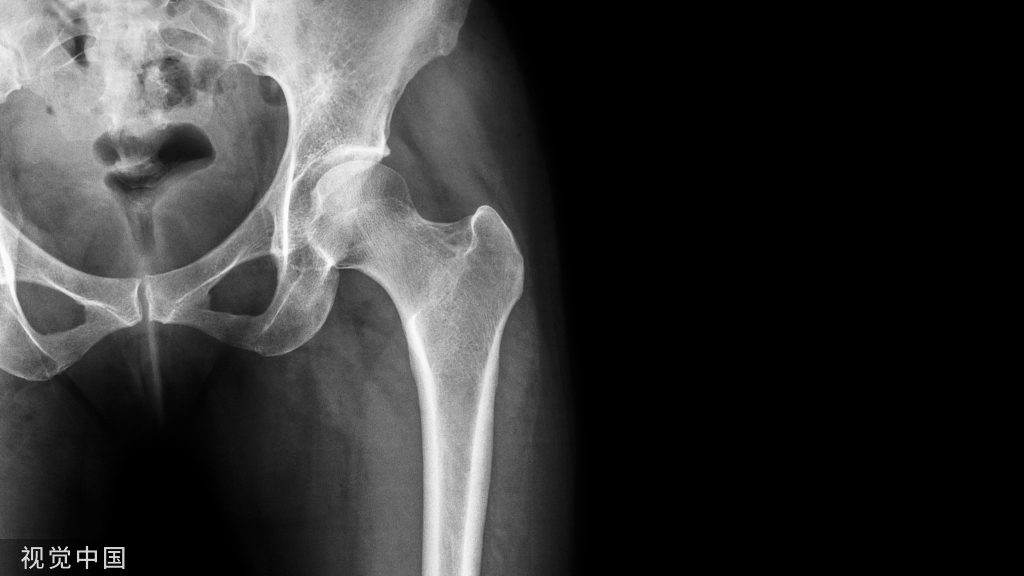

骨质坏死:是骨组织局部代谢的停止,坏死的骨质称为死骨。

死骨形成的原因主要是血液供应的中断。组织学上的表现是骨细胞死亡、消失和骨髓液化、萎缩。早期,骨小梁和钙质含量无何变化,此时X线上也无异常表现。当血管丰富的肉芽组织向死骨推进,则出现破骨细胞对死骨的吸收和成骨细胞的新骨生成,这一过程延续时间很长。

死骨的X线表现是骨质局限性密度增高,其原因有二:其一是周围骨质疏松,死骨相对性的密度增高;其二是死骨骨小梁表面有新骨形成,骨小梁增粗,骨髓内亦有新骨形成,即绝对的密度增高。死骨的形态因疾病的发展阶段不同而不同,随着病程的延长,死骨可逐渐被吸收。恶性肿瘤的残留骨有时为死骨,有时为活骨。